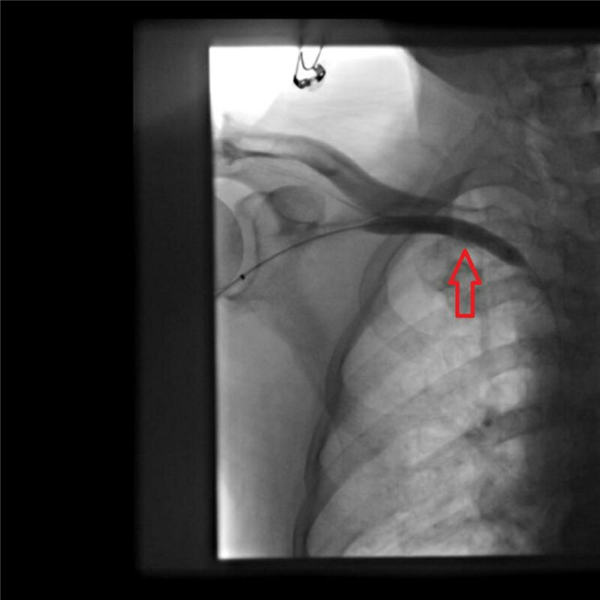

陈力强和赵庆和两位主任经过精心研讨方案,首先通过血管造影,发现右上肢动静脉瘘到上腔静脉共有三处血管明显狭窄(下图红色箭头所示),特别是右锁骨下静脉汇入上腔静脉处更明显,此处血管狭窄造成透析时血液回流障碍、右肩局部血管压力增高,由此引发右肩疼痛。